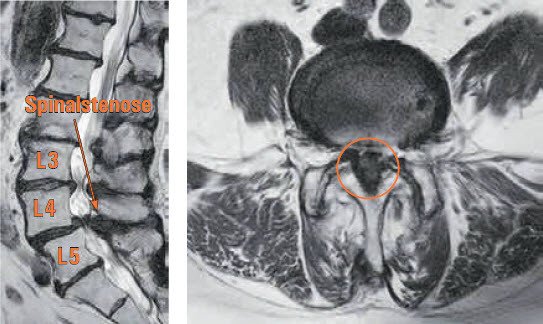

Lumbale Spinalkanalstenose In Der Hohe Lwk 3 4 Und Lwk 4 5 Bandscheibenvorfall De